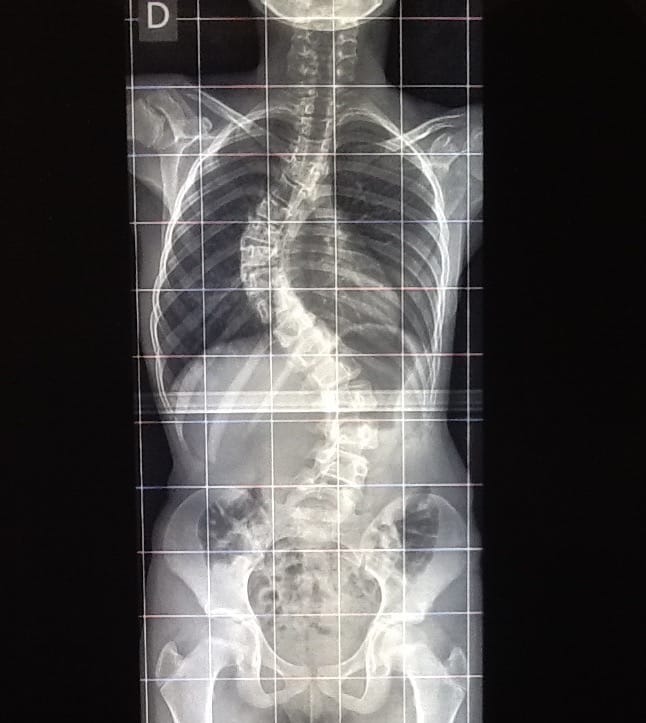

Malattia del Filum e Scoliosi idiopatica nell’adolescenza

La deviazione della colonna vertebrale, conosciuta come Scoliosi o Cifosi idiopatica, è dovuta alla tensione anomala del Filum terminale, definita Malattia del Filum.